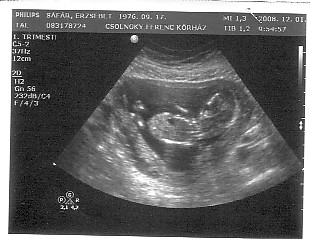

Emma 12 hetes képe 2008.12.01

Emma 12 hetes képe 2008.12.01